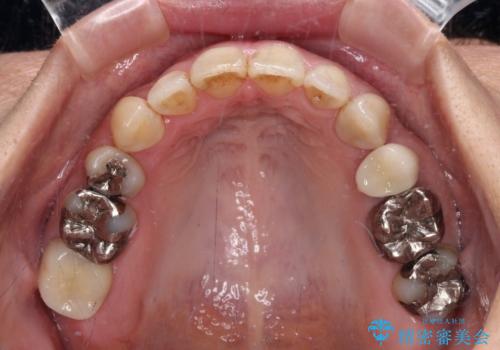

下顎前歯は2本欠損しており、それが原因で隙間ができていました。

また、その影響で上下歯列がアンバランスとなっており、上下前が非接触となっていました。

上下のバランスを取って八重歯などを解消するため、上顎左右第1小臼歯を抜歯することとしました。

根管治療の必要な歯も2本あったため、まずは根管治療を行い、ワイヤー矯正の後に補綴治療を行うこととしました。